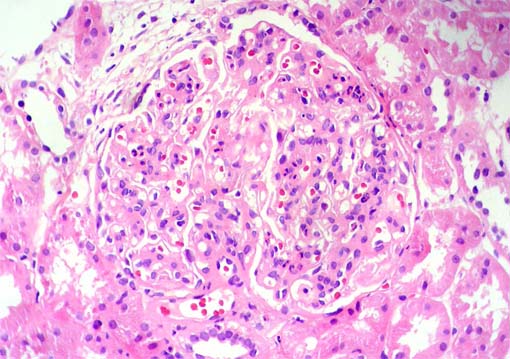

Figura 2.

H&E, X400.